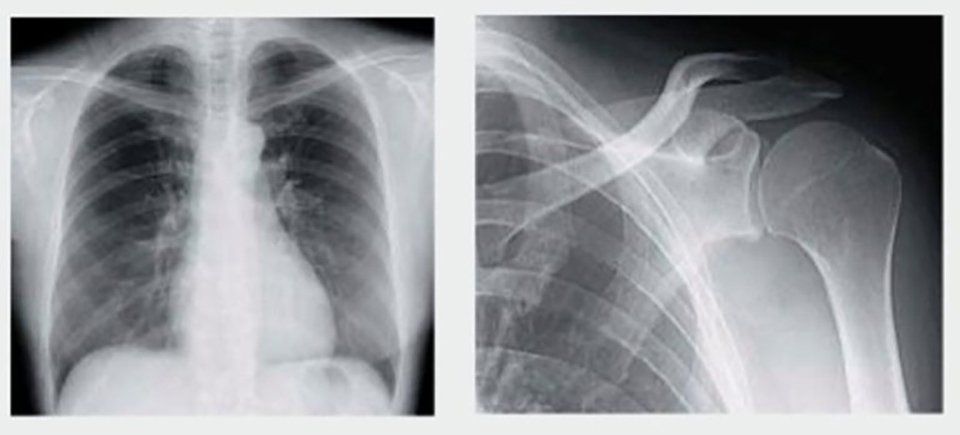

I referti medici sono dattiloscritti su carta intestata e riportano numero di archivio, data, timbro e firma del medico; vengono consegnati nello stesso giorno di esecuzione delle prestazioni di ecografia (al massimo entro 1 ora), dopo 3-4 giorni lavorativi per le prestazioni di radiologia e DEXA ed R.M. È possibile ritirarli negli orari di apertura della segreteria-URP, punto di accettazione e ritiro referti medici dello Studio Radiologico Dr. Tirelli di Altamura.